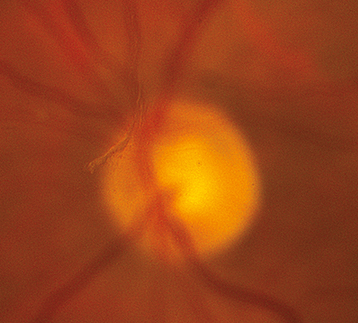

One or more discrete near-translucent or light gray vitreous opacities, one often in the shape of a ring (Weiss ring) or broken ring, suspended over the optic disc (See Figure 11.1.1).

Visualize the PVD at the slit lamp with a handheld lens by identifying a gray-to-white ring or broken ring suspended in the vitreous. If not visible, have the patient make rapid saccades and then look straight to float the PVD into view.